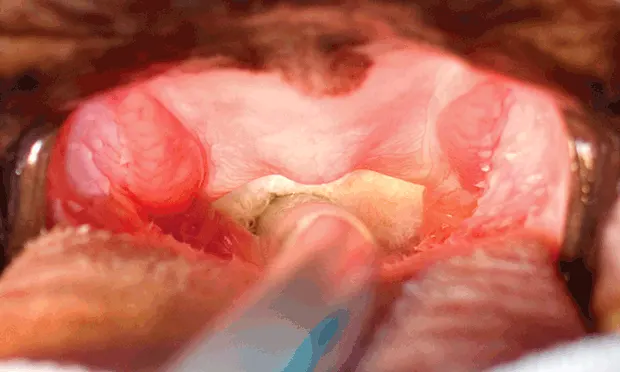

Early surgical correction of these abnormalities is often recommended and commonly includes treatment for stenotic nares and ESP. Other abnormalities (eg, laryngeal collapse2) occasionally require surgical attention but rarely in first intention. ESP, the most consistent anatomic abnormality encountered in dogs with BS, has been reported in up to 100% of cases.3,4 Initially, ESP was primarily described as excessive soft palate length, which can cause obstruction of the rima glottidis on inspiration (laryngeal obstruction). However, in many brachycephalic dogs, it has long been observed5-11 and recently demonstrated12,13 that the soft palate is also excessively thick, adding nasopharyngeal and oropharyngeal components to airway obstruction.

Conventional surgical techniques for eSP correction often consist of a simple resection of the redundant portion of the soft palate using different devices and various resection landmarks; although these techniques address the laryngeal component of obstruction, they may fail to fully address nasopharyngeal and oropharyngeal obstructions.14-26 FFP can address all components of the obstruction by reducing the soft palate’s length and thickness. The use of bipolar cautery in FFP increases intraoperative comfort. Compared with conventional staphylectomies, the suture material is more rostral and therefore farther from the pharynx, which should result in less postoperative pharyngeal inflammation and edema. Also, the rostroventral traction exerted on the remainder of the soft palate tends to further widen the nasopharyngeal opening. FFP tends to be longer and more technically demanding than conventional staphylectomy.